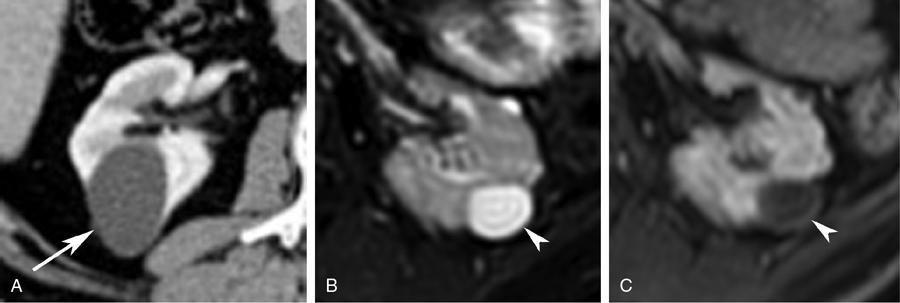

- Imaging: Bosniak type III cysts are indeterminate cystic masses with thick irregular wall or septae, showing measurable enhancement (Fig. 10.12.1.5). Apart from RCC, differential for Bosniak type III cysts are cystic nephroma (Fig. 10.12.1.6), benign multiloculated cyst, mixed epithelial and stromal tumour (MEST), renal abscess and haemorrhagic cyst.

- Imaging: Bosniak type IV cysts are characterized by the presence of enhancing soft tissue nodule (Fig. 10.12.1.7).